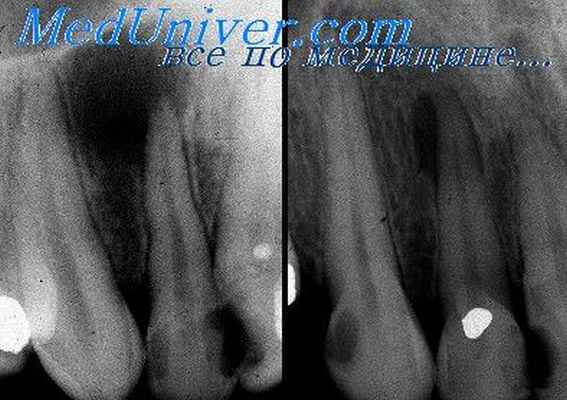

Как правило, киста зуба обнаруживается абсолютно случайно – во время профилактического осмотра или лечения соседнего зуба. Заболевание выявляется рентгенологически.

На снимке видно круглое темное пятно, имеющее четкие контуры, располагается у верхушки корня зуба (окружает его в виде «нимба»). Если у доктора сомнения насчет того, опухоль это или киста, он отправляет пациента на пункцию кисты. В этом случае киста прокалывается, иглой делается забор жидкости и она проходит гистологическое исследование на принадлежность клеток к раковым.